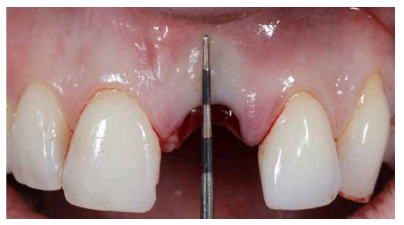

Se evaluó a través de la cucharilla de legrado tipo Lucas y una sonda periodontal CP12, el estado del alveolo, que se encontraba intacto en su totalidad, a excepción de la región vestibular, en la que existía un defecto en sentido coronal-apical de 4 mm (Figura 4).